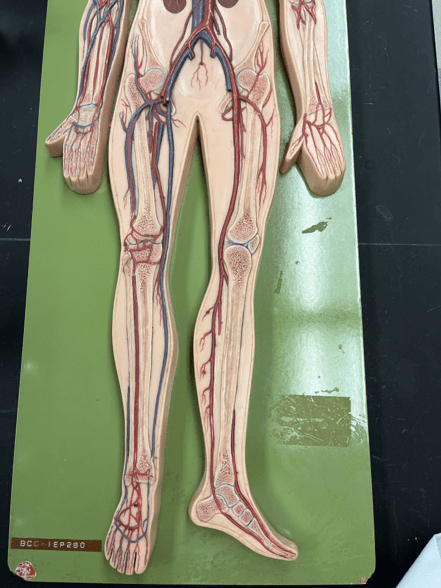

11

New cards

endothelium

• Part of the tunica interna.

• Composes a smooth inner surface of the vessel.

• Composes a smooth inner surface of the vessel.

12

valve

• Found in some veins.

• Establishes unidirectional flow of blood.

• An artery of the head and neck.

• Originates from the brachiocephalic trunk (R.) or the aortic arch (L.).

• Supplies the head and neck through its branches.

• Originates from the brachiocephalic trunk (R.) or the aortic arch (L.).

• Supplies the head and neck through its branches.